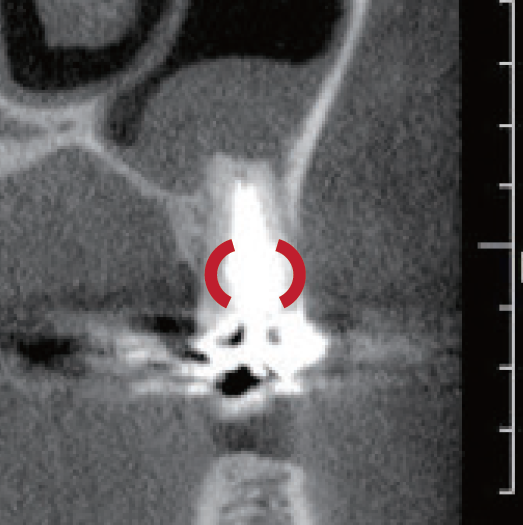

臨床症例3 その4

左上1番の根尖部にMTA製剤充填時のCBCT像

唇側皮質骨は大きく開窓し、根尖病変の大きさが鼻腔底付近まで広がっていることが確認できる

臨床症例3 その5

術後1年のCBCT像

根尖周囲に見られた根尖病変はほぼ消失し、唇側皮質骨の開窓も改善したことが認められる